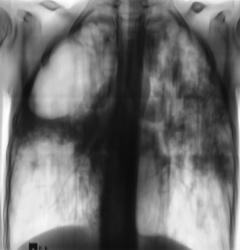

А вот тубер ещё круче, Валентин Львович. Пациентке 29 лет.

От правого легкого осталось едва ли 1,5 сегмента. Легочные сосуды чуть ли не в воздухе висят.

Пациентка асоциальна, её "мир" совсем иной и почти не пересекается с нашим. Так что, произошло такое элементарно, когда она проходила флюорографию никто не знает, включая её, никто не виноват. Подчеркиваю последнее - никто не виноват (без нас найдутся умники и обвинят врачей, да ещё и рентгенологов).